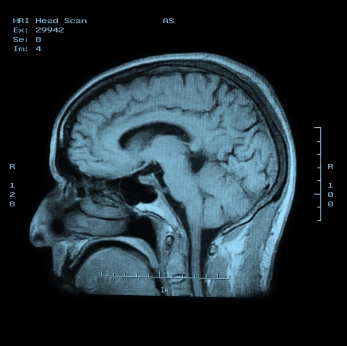

МРТ головного мозга без красителей

МРТ является магнитно-резонансная томография, специальный тест визуализации, которая не использует рентгеновских лучей. Эта процедура дает очень подробные изображения мозга, структуры лица, и пазух. В целом, МРТ лучше на выявление острых инсультов, инфекций и раковых заболеваний, чем компьютерная томография.